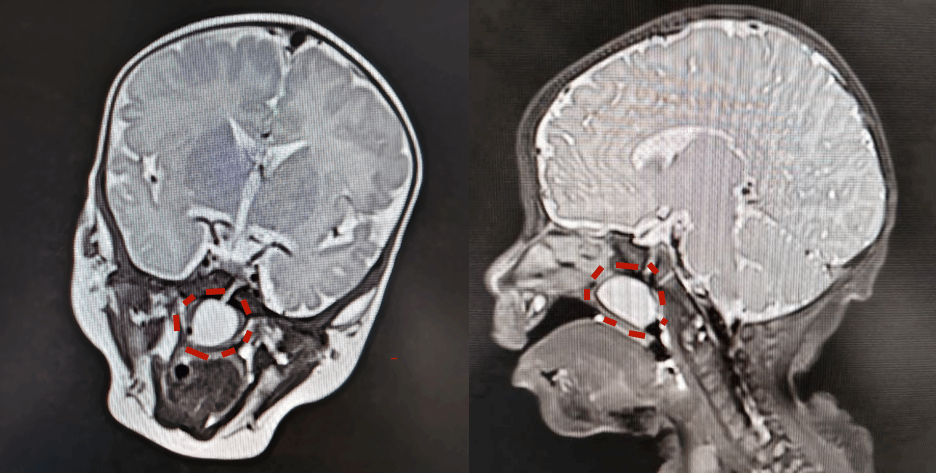

小西入院后,科室迅速启动多学科协作机制。电子鼻咽喉镜检查发现,鼻咽部新生物堵塞双侧后鼻孔;CT与MRI精准定位鼻咽部病灶(大小约13.3mm×21.1mm×20.7mm),明确其与蝶骨斜坡缝隙的关联,为手术方案制定提供关键依据。

电子鼻咽喉镜显示膨出的脑膜

MRI图像:红圈位置为膨出的脑膜